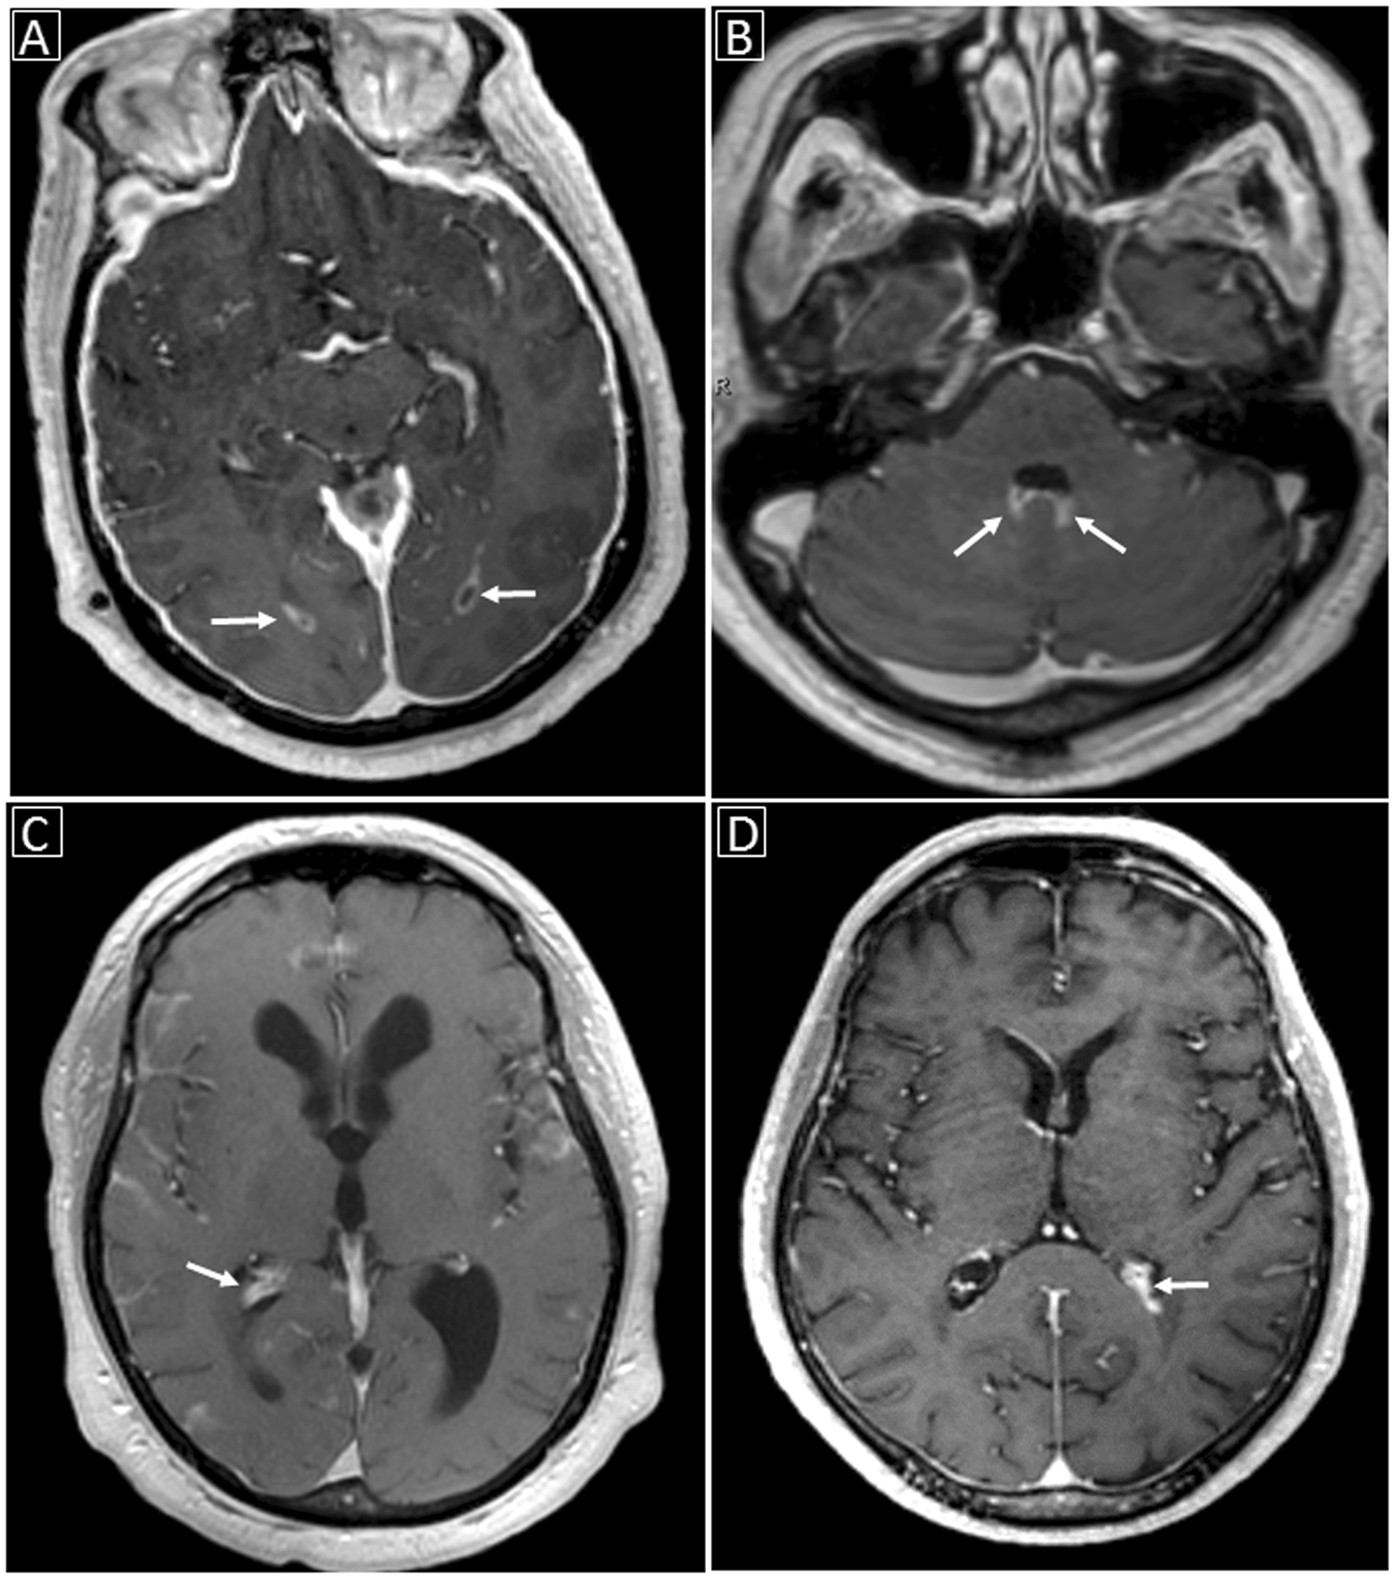

Figure 2

Examples of ventricular involvement in CNS cryptococcosis: (A) Abnormal ependymal enhancement along the occipital horns of the lateral ventricles bilaterally (white arrows) on enhanced T1-weighted image; (B) Abnormal ependymal enhancement along the posterior aspect of the fourth ventricle with probable associated choroid plexitis (white arrows); (C) Choroid plexitis of the right lateral ventricle (white arrow) with hydrocephalus; (D) Left lateral ventricular choroid plexitis (white arrow).